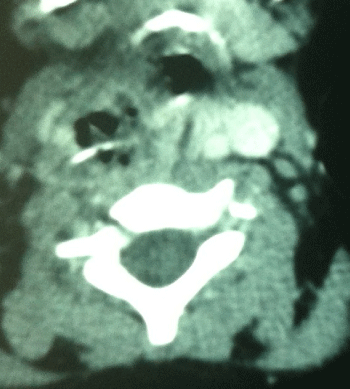

Neck x-ray revealed linear radio opacity suggestive of a foreign body at the level of C5-6 vertebrae. A computed tomography (CT) scan was then done that showed a 2cm long metallic foreign body in the subcutaneous tissues of neck at the level of C5-6 vertebrae (Figure 1,2).

Figure 1: CT axial image of neck showing the metallic foreign body.